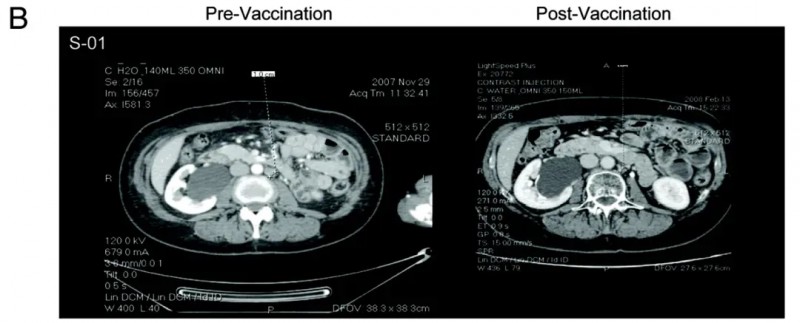

值得一提的是,S-01号患者的治疗效果尤为突出,该患者在接种疫苗后至少达到病情稳定(SD),对比接种DC疫苗前的CT影像(左图)与接种后的影像(右图),可见其左主动脉旁淋巴结出现退化(详见下图)。

▲图源“Oncoimmunology”,版权归原作者所有,如无意中侵犯了知识产权,请联系我们删除